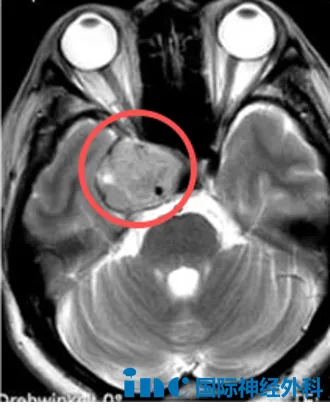

26岁女性右侧丘脑病变患者

女性患者芝芝,右侧丘脑病变,尺寸约25mm×23mm×24mm,虽无显著临床症状,但既往有鞍区生殖细胞瘤放化疗史。本次她希望手术彻底切除丘脑病变。“对我而言属常规手术。”面对面咨询时巴教授的自信使她对手术充满信心。